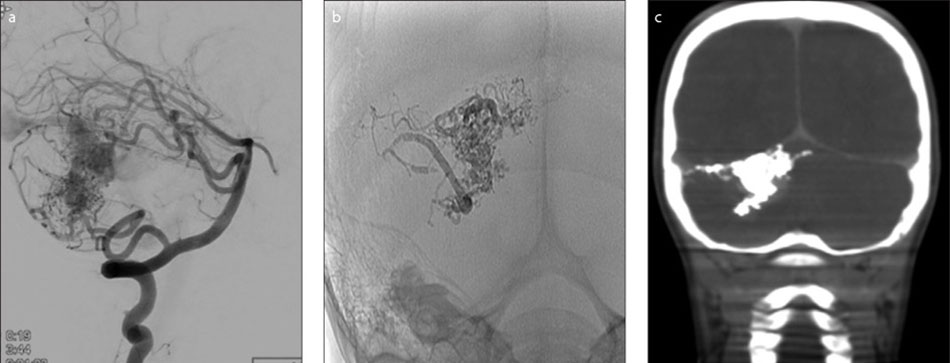

Arteriovenous malformations (AVM)

Arteriovenous malformations are abnormal collections of blood vessels, where arteries are directly connected to veins. Normally blood flows through arteries under high pressure to supply all of the organs of the body including the brain. From the arteries, blood passes through thin-walled capillaries to supply oxygen and nutrients to the tissue of the brain and then enters the veins under low pressure to be carried back to the heart and lungs.

In an AVM, the blood flows from the arteries directly to the veins. There is no capillary bed. Without a capillary bed, the AVM blood vessels have an increase in flow and blood pressure. Over the years this causes them to dilate and become thin-walled, and more likely to break and bleed.

An AVM can cause headache, weakness, numbness, visual problems, or seizures. Patients often first show symptoms when there is a bleed or rupture from one of the blood vessels making up the AVM.

An AVM is often diagnosed with a CT scan or MRI. A patient usually requires an angiography to then fully identify the anatomy of the AVM and make decisions about treatment.

AVMs may be treated using three different treatment methods. These methods are embolization, surgery and radiation therapy or radiosurgery.

Endovascular treatment of AVMsis available at FV Hospital. One innovative form of treatment involves use of a “super glue” substance introduced via a tiny catheter to reduce the size of the AVM and facilitate further microsurgical or radiation treatment. In some cases, it is possible to completely block off and cure the AVM with endovascular treatment alone.